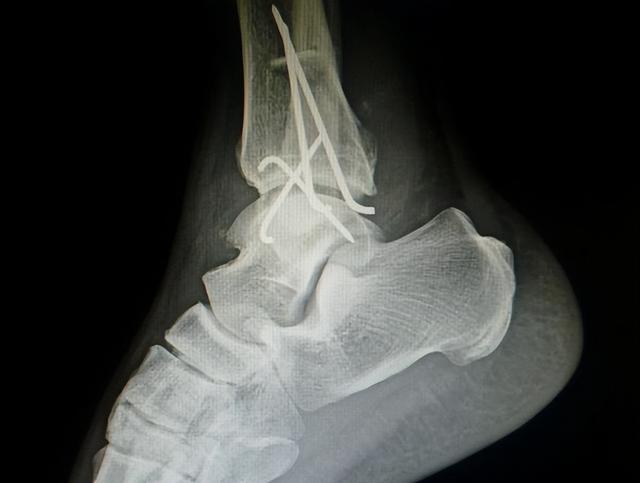

“崴脚” , 即踝关节扭伤 , 是一种常见的运动损伤 , 常发生在下台阶和对抗性运动(如:打篮球)过程中 。 当脚下不稳或受到外力冲击时 , 踝关节可能被迫出现大幅度的外翻或内翻 , 使相应的韧带遭受过度牵拉 , 导致其扭伤甚至断裂(如下图所示) 。 多数情况下 , 通过休息和静养能够消除症状 , 但却难以避免患侧力量萎缩、协调性变差、运动能力下降等问题 。 在缺少康复训练介入的情况下 , 还可能会演变为习惯性崴脚 , 增加踝关节骨折等运动损伤的风险 。

初一的时候 , 孩子以为问题不大 , 继续去打球 , 不承想在跳起并落地时再次崴脚 , 并不幸引发踝关节粉碎性骨折 , 前后经历三次手术方才修复 , 历时半年之久 , 身心遭受深远影响 , 成绩也从班级前三掉到前十 。 在医生的建议下 , 家长带孩子前来寻求运动康复方面的帮助 。 我们对孩子的情况进行综合评估后认为 , 即便之前的手术治疗是成功的 , 如果不进行系统性的康复训练 , 孩子以后不仅要告别篮球之类的剧烈运动 , 连平常的跑跳恐怕都要小心 , 否则依然会导致旧伤复发 。 孩子尚且如此 , 更何况别人?